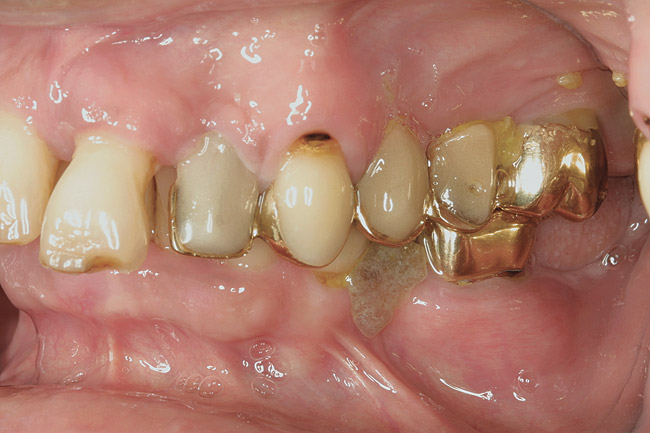

Figure 4  This root surface is black and cavitated. When exploring with the side of the explorer, this root surface will feel soft and sticky, and it may be possible to remove soft debris from this lesion.

Figure 4